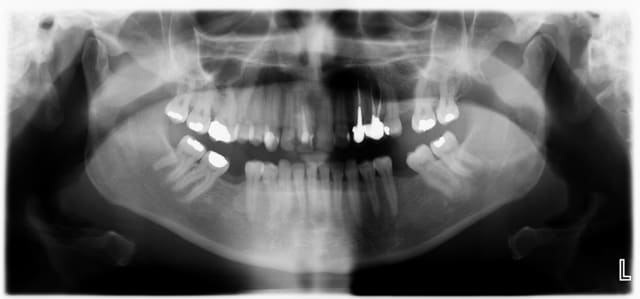

Ca c'est un boulot qui m'a fait extrêmement plaisir, parce que je trouve qu'on touche là à l'essence même de notre activité: permettre aux gens de manger.

Ce monsieur, 80 piges au compteur, est arrivé avec des vieilles provisoires, des gros compos, tout se cassait la figure... "Oh, mais à mon âge est-ce que ça vaut bien le coup de mettre des sous dans les dents..."

Pas de vraies difficultés techniques, pas de recherche esthétique marquée, du métal, on a reconstruit une occlusion de 5 à 5 seulement. Mais niveau qualité de vie, j'aimerai être toujours aussi efficace.

Photos un an après la pose. Pano avant.